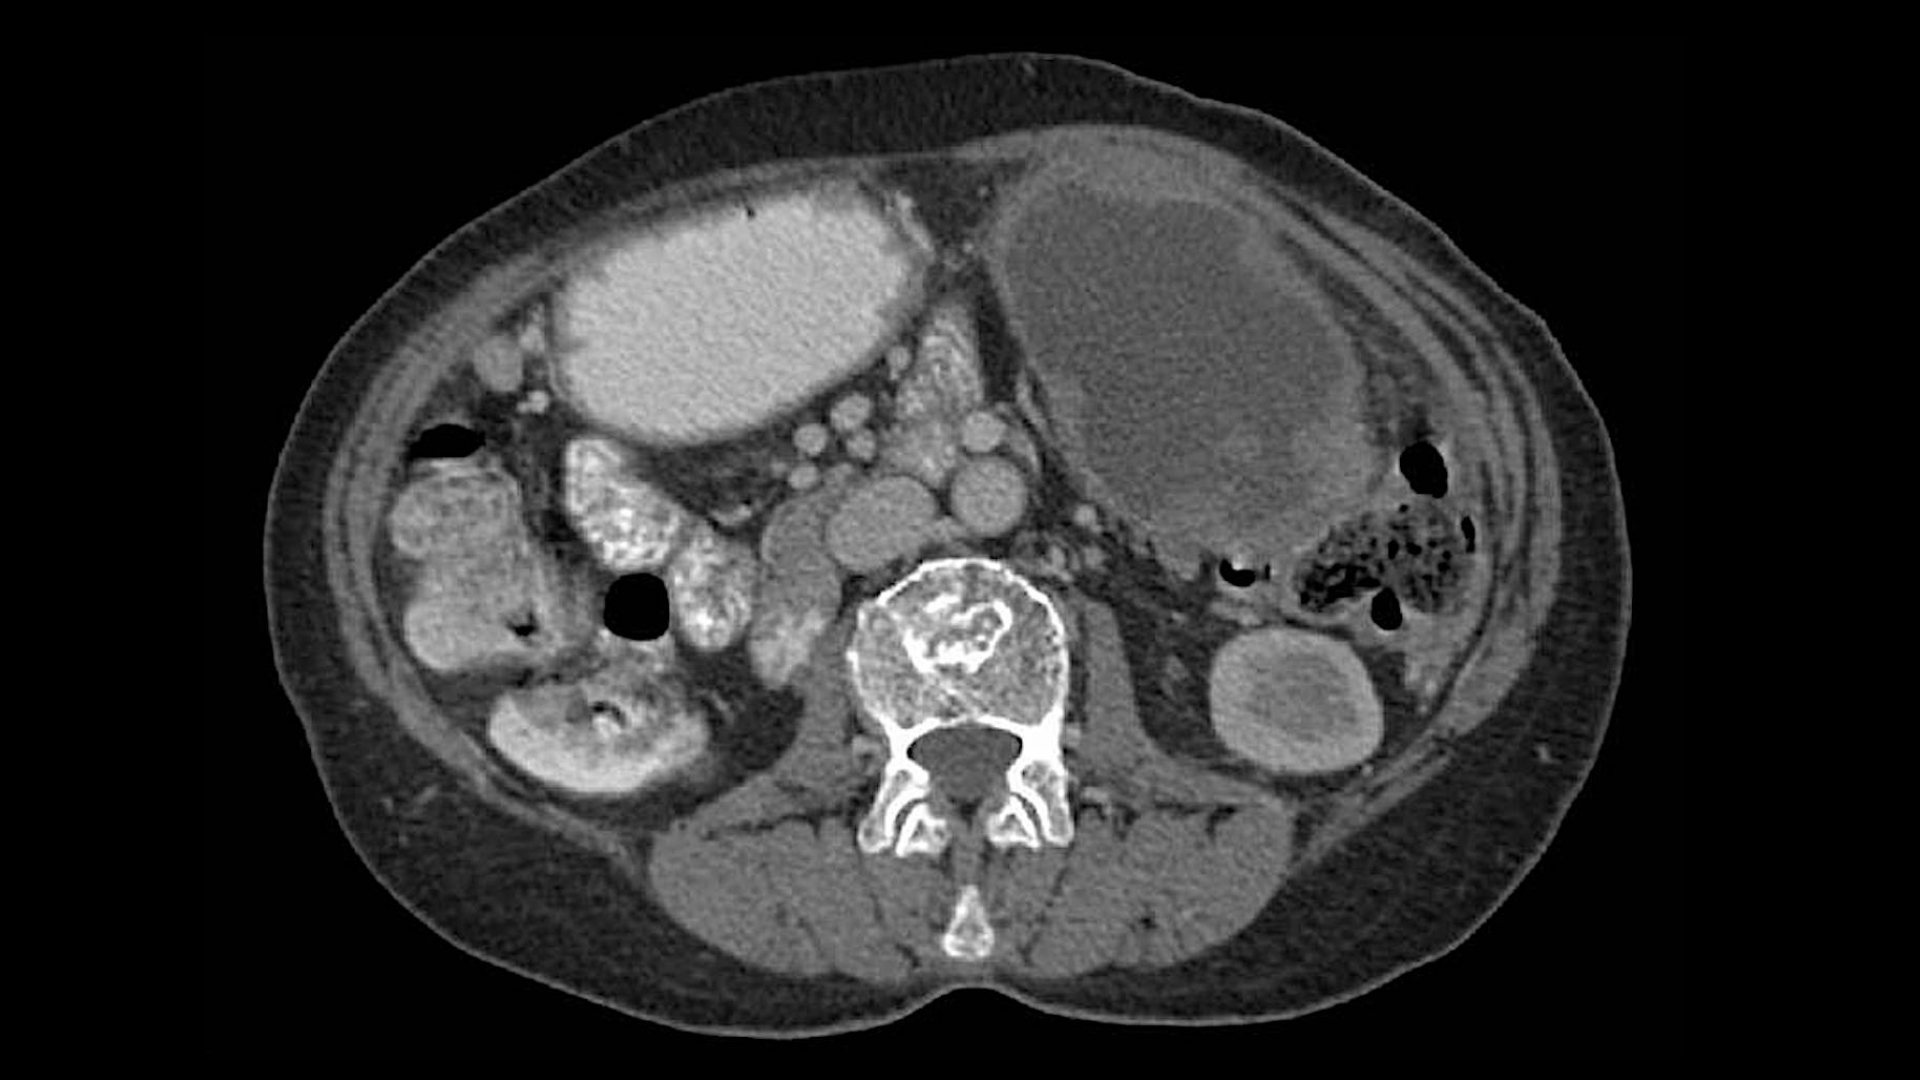

• Advanced Diagnostics: State-of-the-art imaging (e.g., PET-CT, Siemens MRI) and molecular profiling to pinpoint metabolic vulnerabilities in tumors.

• Medical Records: Recent diagnostic reports, imaging scans (e.g., CT, MRI, PET-CT), pathology results, and treatment history. Digital or physical copies are accepted.